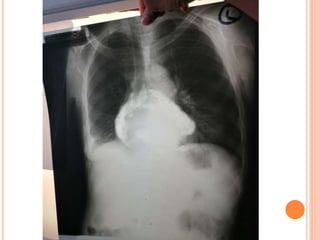

INVESTIGATIONS (SPECIFIC FINDINGS)

 Xrays

 CT